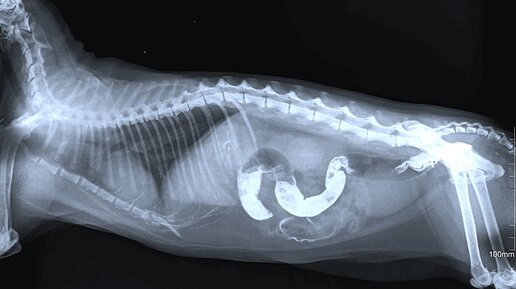

Второе обследование прошло быстрее. Рассматривая «стереокартинки» на экране, доктор сказала, что Тигре светит рентген с контрастом. Рентген с контрастом Сначала делают снимок без лекарства. И, поехали. Вещество, введенное для контраста, – сульфат бария. Может быть в виде порошка, пасты, суспензии. Тигре он достался в виде чего-то, разведенного в кефире. Принцип действия. Барий подсвечивает исследуемые органы белым цветом (в нашем случае – область ЖКТ). Животинке выпаивают барий и несут делать снимок...